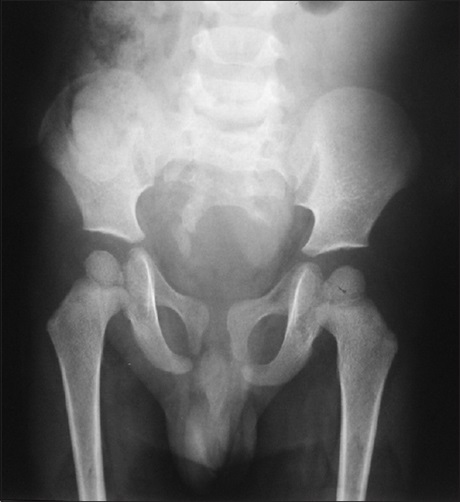

We describe the first documented radiologic findings of complete Currarino triad presenting as neonatal intestinal obstruction in a

Nigerian male child. A 1-week-old male neonate was admitted for rectal agenesis and had a divided colostomy during which an anterior sacral meningocele was discovered intraoperatively. The imaging evaluation revealed further, the triad of a partial sacral defect, anorectal atresia, and anterior sacral meningocele. These radiologic findings define the rare association known as the Currarino

syndrome (CS). The CS expresses a wide phenotypic expression, and so its diagnosis may be elusive. This case emphasizes the need for physicians to be cognizant of the clinical presentation and radiologic findings of CS. It is a triad to remember in infants with anorectal malformations and even older children or adults presenting with chronic constipation.